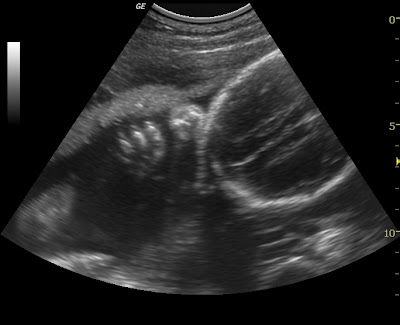

Cheyenne snuggled in there real good.

The top of her head

A shot of her arm